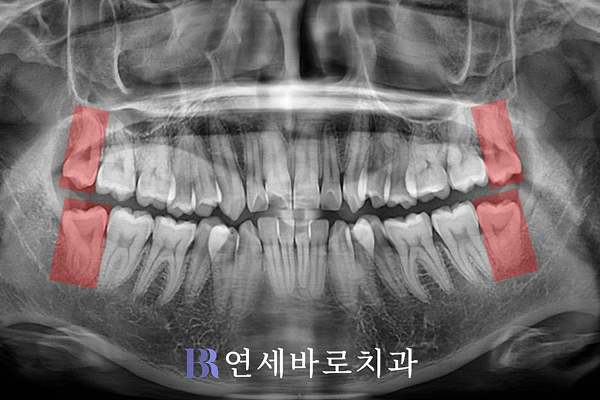

전체적으로 치아 배열이

가지런하지 못한 편이었으며,

특히 앞니의 전방 경사가

뚜렷한 것으로 나타났습니다.

상악과 하악 모두 전치부 쪽

치열이 불규칙한 편이며,

특히 아랫니의 좌우 양쪽에서

제1소구치가 안쪽을 향해

들어간 모습이 확인됐습니다.

전체적인 악궁의 너비가

좁은 케이스로 볼 수 있으며,

특히나 아래쪽의 폭경이

심각할 정도로 비좁았습니다.

물론 이로 인하여 기능적인

문제점도 관찰됐는데요.

하악의 작은 어금니 2곳이

안으로 많이 들어와 있는 만큼

측면 교합이 불안정하게

형성된 모습을 발견하였습니다.

이를 위해 소구치 4개를 전부

발치하기로 결정하였으며,

추가로 양쪽 사랑니 4곳 또한

안전하게 제거하였습니다.